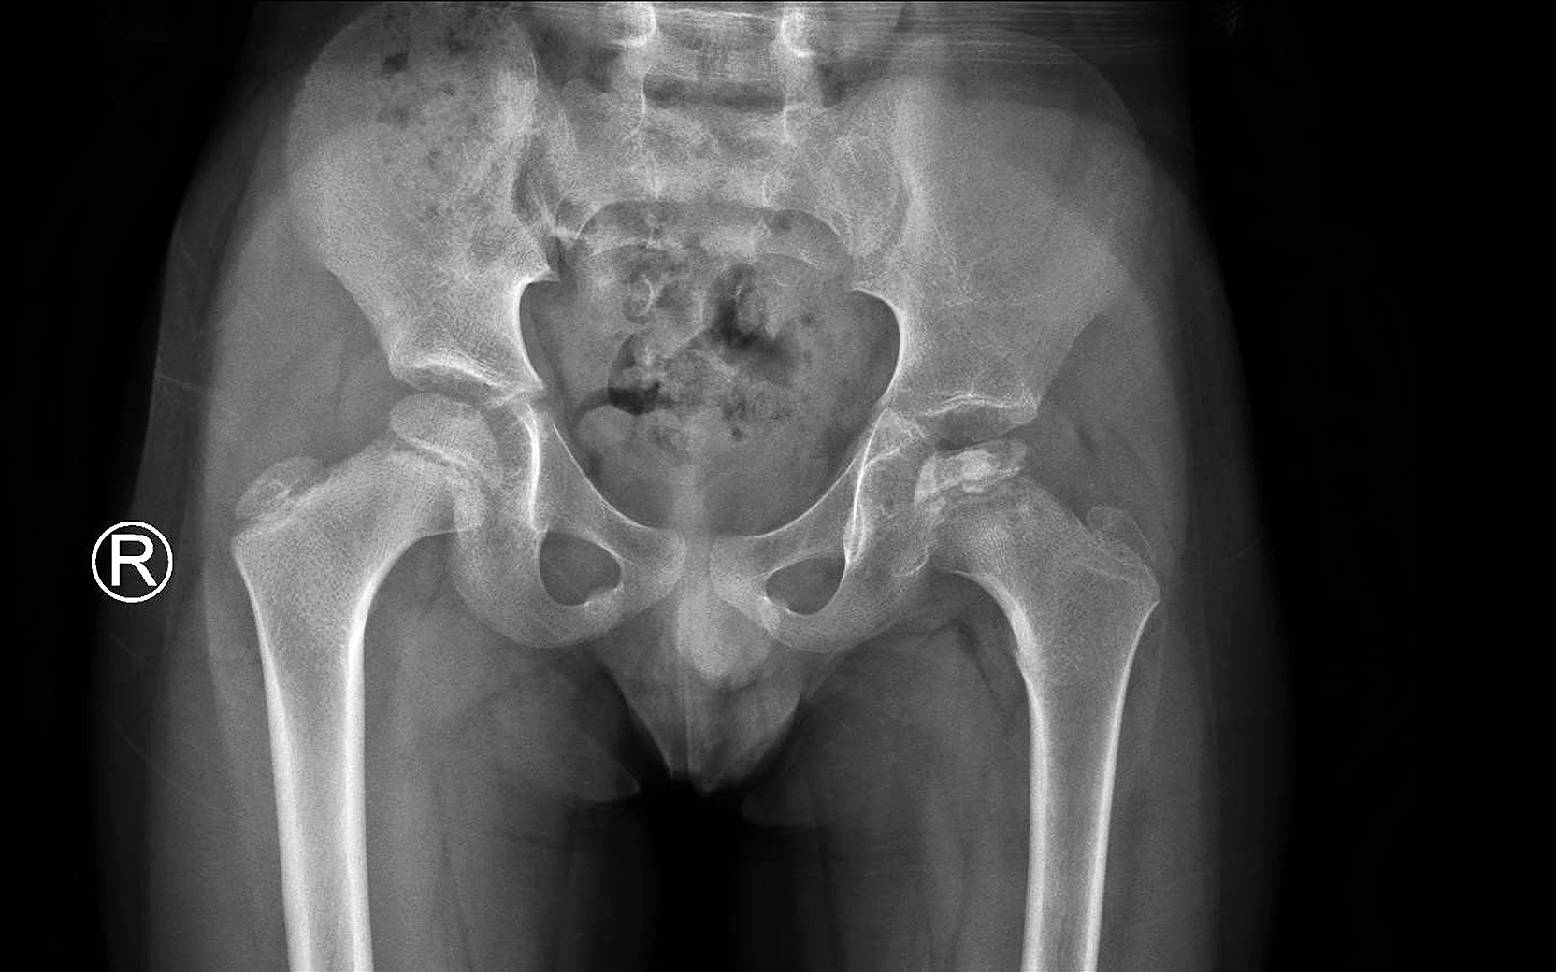

Nach einem ausführlichen Vorbericht und einer eingehenden klinischen Untersuchung kann der behandelnde Tierarzt meist bereits eine erste Verdachtsdiagnose stellen. Um die Diagnose zu bestätigen und andere sich ähnlich äußernde Erkrankungen auszuschließen, wird in den meisten Fällen eine zusätzliche Röntgenuntersuchung durchgeführt. Auf dem Röntgenbild lassen sich der Gelenkspalt, die Wachstumsfuge, sowie der Zustand des Oberschenkelkopfes genau beurteilen.